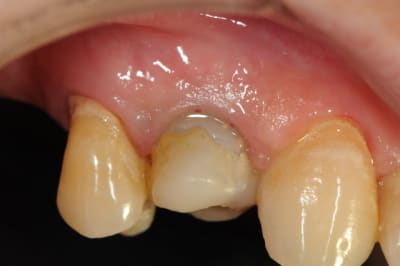

11 avec résorption interne

EII avec MCI sur du dentium (4.5/14) comblement du gap vestibulaire avec du kasios tcp (très constant dans les résultats...et très économique)

pas de photos de chir par contre...j'ai du les effacer par erreur...grrrr...

la prothèse d'usage a été réalisée par ma petite associée...mais j'étais là pour superviser et faire quelques photos...;-)